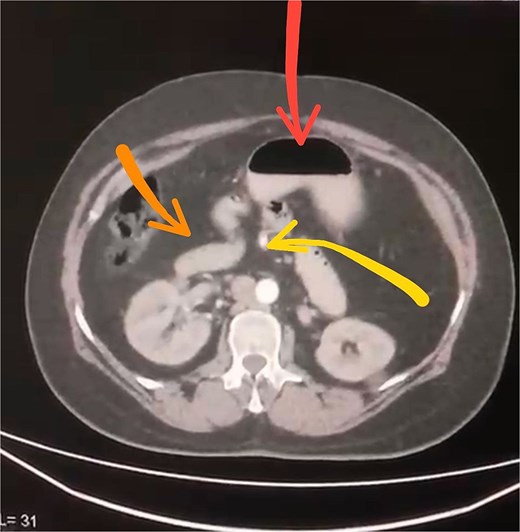

Initial imaging with a plain abdominal X-ray showed non-specific gas patterns without obstruction (Fig. 1). Contrast-enhanced CT revealed features of intestinal non-rotation, including abnormal duodenal positioning and atypical mesenteric vessel orientation. The sagittal view showed a retromesenteric duodenum without volvulus or bowel wall compromise (Fig. 2), while axial images demonstrated a reversed superior mesenteric artery (SMA)–superior mesenteric vein (SMV) relationship (Fig. 3), supporting malrotation. These findings are further illustrated in Supplementary Video S1), showing small bowel on the right, colon on the left, retromesenteric duodenum and abnormal SMA–SMV positioning. Colonoscopy showed normal mucosa without obstructive lesions.

Axial contrast-enhanced CT scan demonstrating abnormal positioning of abdominal structures: The stomach is seen in the upper center (arrow), the duodenum crosses the midline anteriorly (arrow), and the superior mesenteric artery lies abnormally to the right of the superior mesenteric vein (arrow).